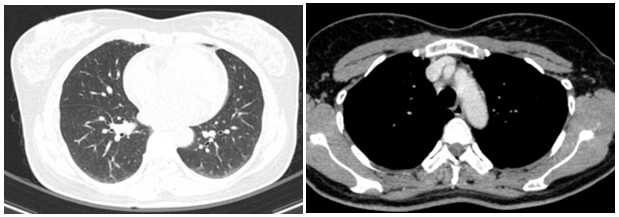

Siêu âm:

Thùy phải: kích thước bình thường, nhu mô có vài nhân hỗn hợp âm, lớn nhất kích thước 3x3mm và có nhân giảm âm, vôi hóa ngoại vi kích thước 3x4mm (TIRADS 4), nhân đồng âm bờ đều, kích thước 4x6mm.

Thùy trái: kích thước bình thường, nhu mô có vài nhân hỗn hợp âm, bờ đều, lớn nhất kích thước 8x9mm (TIRADS 3).

Hình 1: Hình ảnh nhân giảm âm thùy phải tuyến giáp (TIRADS 4)